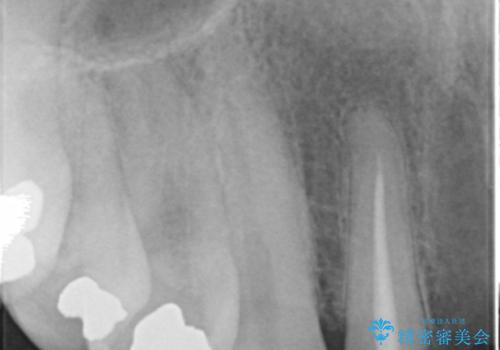

- お風呂場で転んで上の前歯が2本抜けてしまったことを主訴に来院された患者様です。

精査したところ、左上の側切歯(左上2)も破折しており保存不可能な状態でした。

左上の側切歯(左上2)を抜去し、右上の側切歯(右上2)の再根管治療後、セラミックのブリッジによる補綴を行いました。